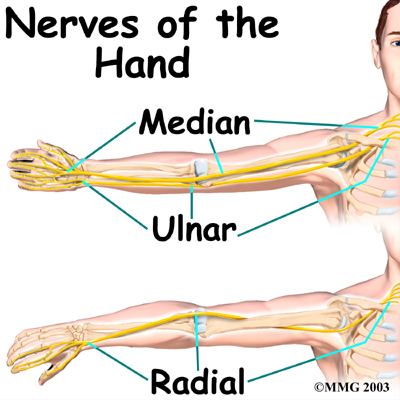

All of the nerves that travel to the hand and fingers begin together at the shoulder: the radial nerve, the median nerve, and the ulnar nerve. These nerves carry signals from the brain to the muscles that move the arm, hand, fingers, and thumb. The nerves also carry signals back to the brain about sensations such as touch, pain, and temperature.

The runs along the thumb-side edge of the forearm. It wraps around the end of the radius bone toward the back of the hand. It gives sensation to the back of the hand from the thumb to the third finger. It also supplies the back of the thumb and just beyond the main knuckle of the back surface of the ring and middle fingers.

The travels through a tunnel within the wrist called the carpal tunnel. This nerve gives sensation to the thumb, index finger, long finger, and half of the ring finger. It also sends a nerve branch to control the thenar muscles of the thumb. The thenar muscles help move the thumb and let you touch the pad of the thumb to the tips each of each finger on the same hand, a motion called opposition.

The travels through a separate tunnel, called Guyon's canal. This tunnel is formed by two carpal bones, the pisiform and hamate, and the ligament that connects them. After passing through the canal, the ulnar nerve branches out to supply feeling to the little finger and half the ring finger. Branches of this nerve also supply the small muscles in the palm and the muscle that pulls the thumb toward the palm.